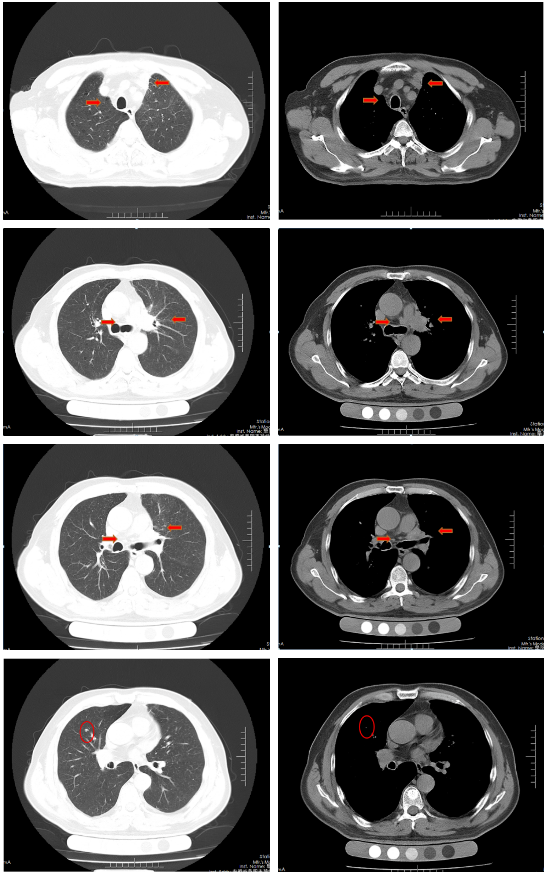

2022-07-28、2022-08-20应用斯鲁利单抗 300mg单药维持治疗。

胸部CT(2022-08-30):双侧肺野透亮度增加,以两上肺和胸膜下明显。双肺纹理增多、增粗,紊乱,左肺上叶见条片状高密度灶,大小29mm×18mm,小叶间隔增厚,两肺下叶见囊状透亮区。气管、左右主支气管无明显狭窄。纵隔内未见肿大淋巴结影。两侧胸腔无明显积液。胸部CT诊断:左上肺门占位复查;慢性支气管炎-肺气肿样改变;两肺下叶肺气肿。

治疗后评价:患者经过斯鲁利单抗单药维持治疗两周期后,患者未再出现咳嗽等症状,体重逐渐增加。影像学提示左肺病灶及纵隔淋巴结及肺门淋巴结、右肺结节基本消失,疗效评价接近CR。